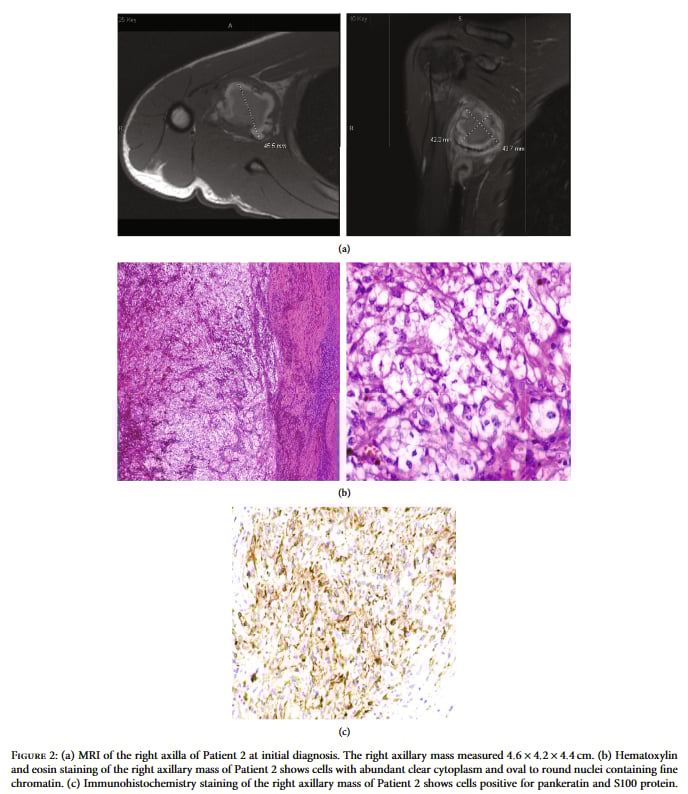

患者情况:一名18岁的青年,四年来右上臂和右手反复疼痛,一年前发现右侧腋窝出现一个肿块。MRI检查显示肿块大小约为4.6×4.2×4.4厘米。

▲图2 初诊时的MRI、HE和免疫组化结果

诊断难题:患者接受了肿瘤切除手术。然而,术后的病理分析再次遇到了挑战。肿瘤细胞的形态和免疫组化特征非常不典型。例如,它表达S100蛋白(常见于神经源性肿瘤),但却不表达黑色素瘤的标志物HMB45和MelanA。FISH检测虽然发现了EWSR1基因存在重排,但这可能指向两种不同的肿瘤:透明细胞肌上皮瘤或透明细胞肉瘤(Clear Cell Sarcoma, CCS)。然而,无论是细胞形态还是免疫表型,都与这两种肿瘤的典型特征不完全相符,诊断再次陷入僵局。

NGS一锤定音:面对这种诊断困境,RNA NGS检测再次发挥了关键作用。检测结果精准地捕获到了EWSR1基因(位于22号染色体)与ATF1基因(位于12号染色体)的融合。这个特异性的基因融合是透明细胞肉瘤(CCS)的分子“身份证”,不容置疑。诊断由此明确。